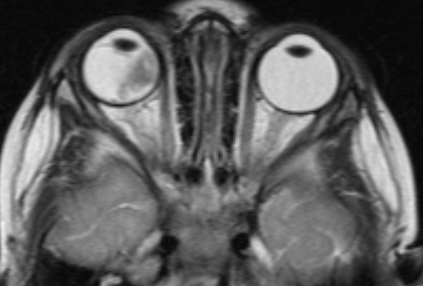

- D - рассеянные опухоли с крупными опухолевыми массами, разнокалиберными отсевами в стекловидном теле и/или субретинальном пространстве в более чем 3 мм от новообразования с субретинальной жидкостью более 6 мм от образования, включая полную отслойку сетчатки (рис. 3 и 4).

![Визуализация ретинобластомы с помощью МРТ. Размеры образования соответствуют клинической группе D]()

Рис. 3. Визуализация ретинобластомы с помощью МРТ. Размеры образования соответствуют клинической группе D